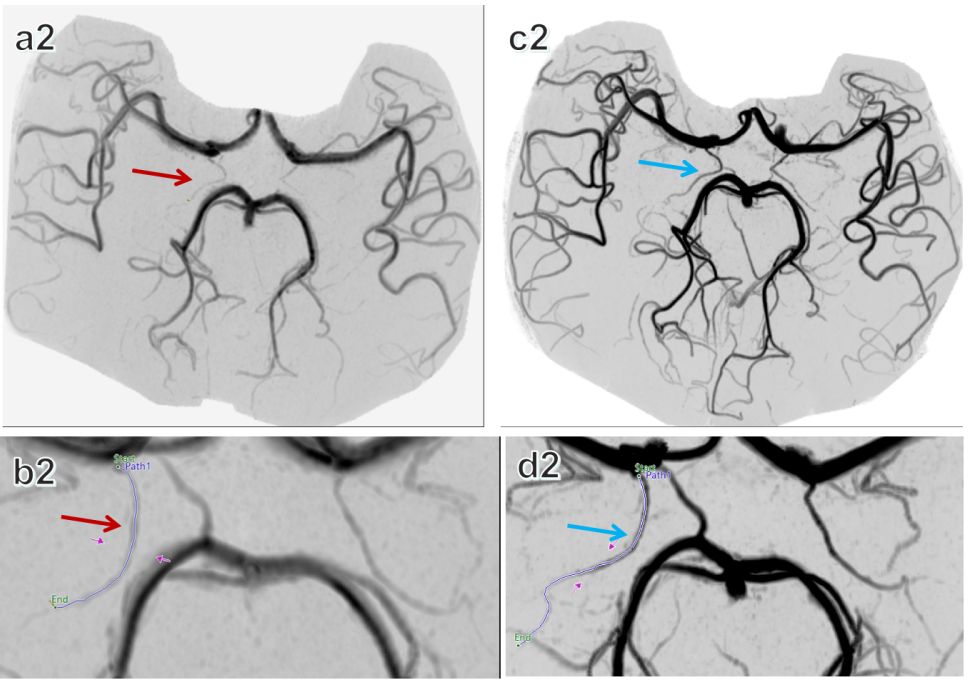

图3. 同一受试者的反色脑部MRA对比。A2和B2图像采用3.0T MR扫描,而C2和D2图像则采用5.0T MR扫描。红色箭头指向3.0T MR成像中可视化的AChA,蓝色箭头高亮显示5.0T MR成像获得的AChA,证明了更高场强图像的卓越清晰度和细节。